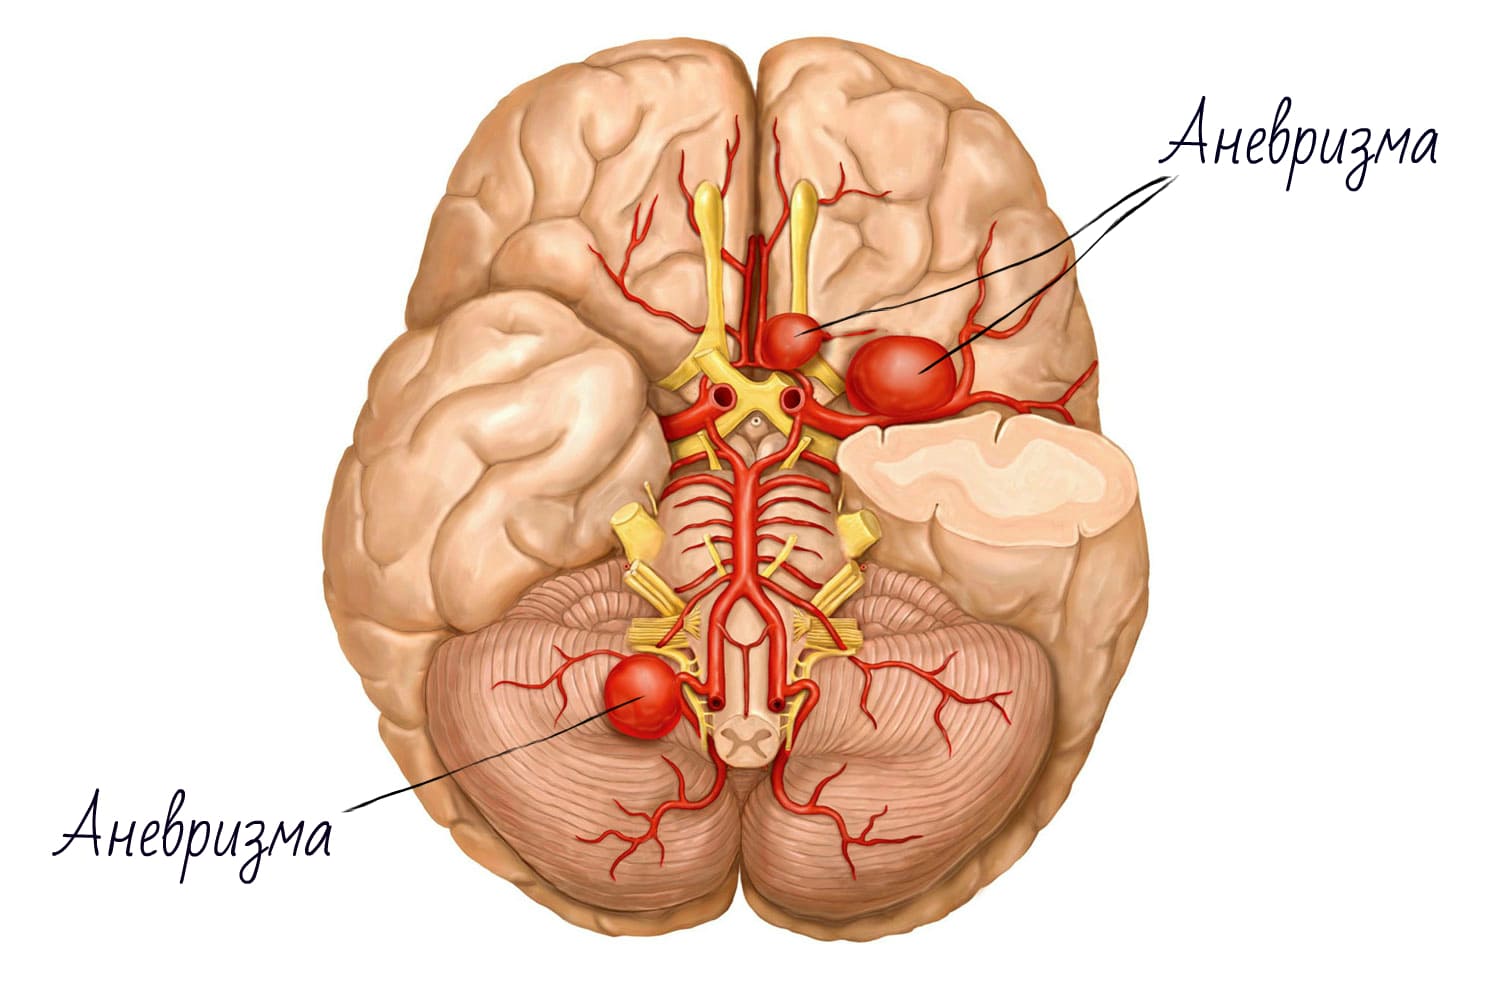

Снимки и иллюстрации микроаневризм сосудов головного мозга

:format(webp):quality(80)/https%3A%2F%2Fwww.csid.ro%2Fwp-content%2Fuploads%2F2020%2F05%2F17889730%2F1-anevrism-cerebral.jpg)